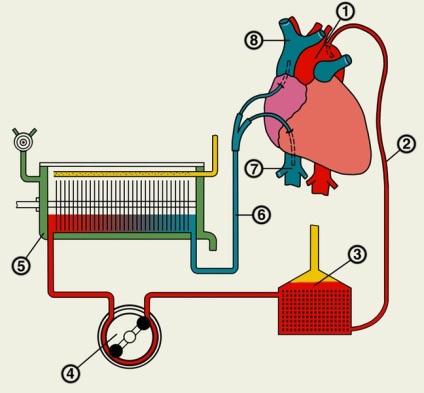

- tahipnee și viteza de creștere a fluxului sanguin. Pacientul este conectat la aparate organe artificiale;

Dacă este necesar, pacientul este conectat la dispozitivele de ventilație și inima artificiala, deoarece organele sale opresc funcționarea normală independentă, reduce volumul de sânge care alcătuiesc soluții de coloidale și cristaloide.